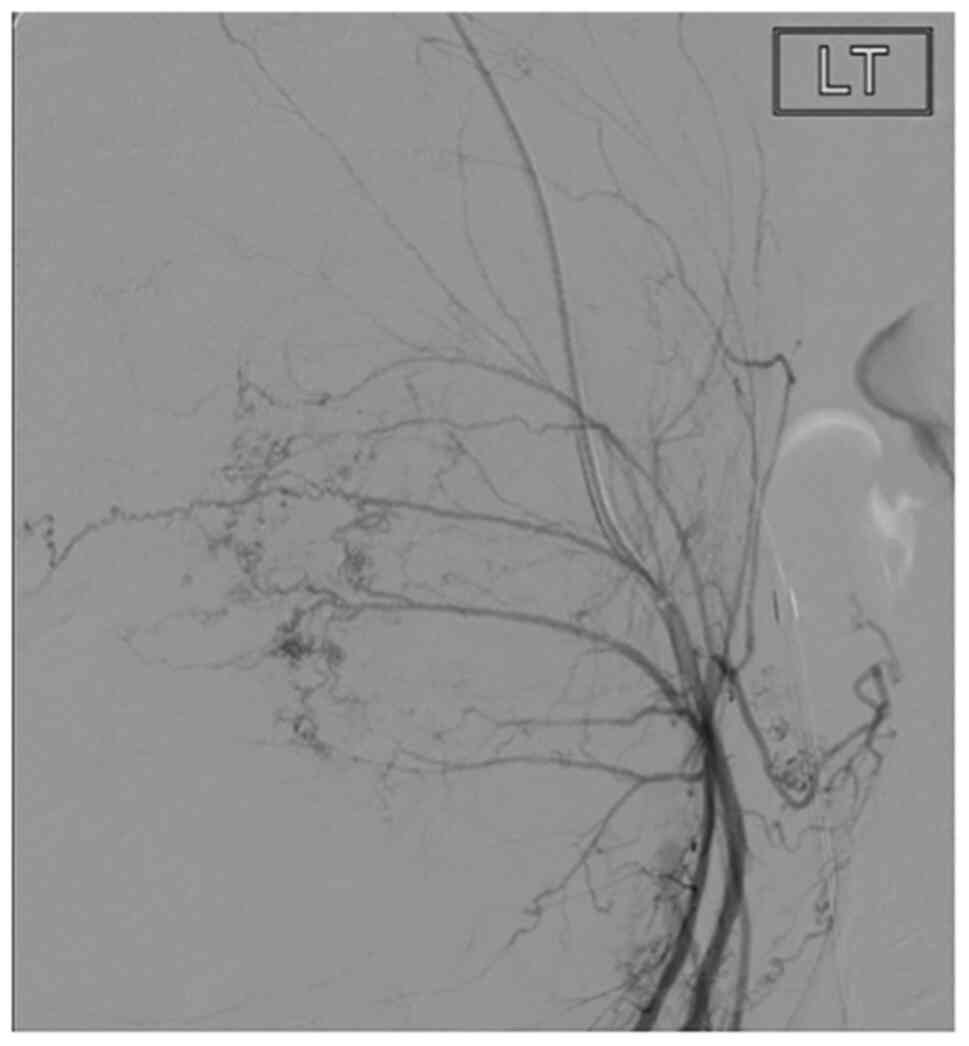

A 27-year-old Eastern European female (gravidity, 1; parity, 0) presented to the Royal Wolverhampton NHS Trust at 12/40 gestation following an abnormal booking scan. The ultrasound findings included a grossly enlarged uterus extending above the umbilicus (113 AP x127 mm), with the uterus filled with a semi solid mass containing cystic areas consistent with the ‘snowstorm’ appearances indicative of a HM (Fig. 1).

Figure 1Transabdominal ultrasound images showing the characteristic ‘snowstorm appearance’ indicative of a hydatidiform mole. |